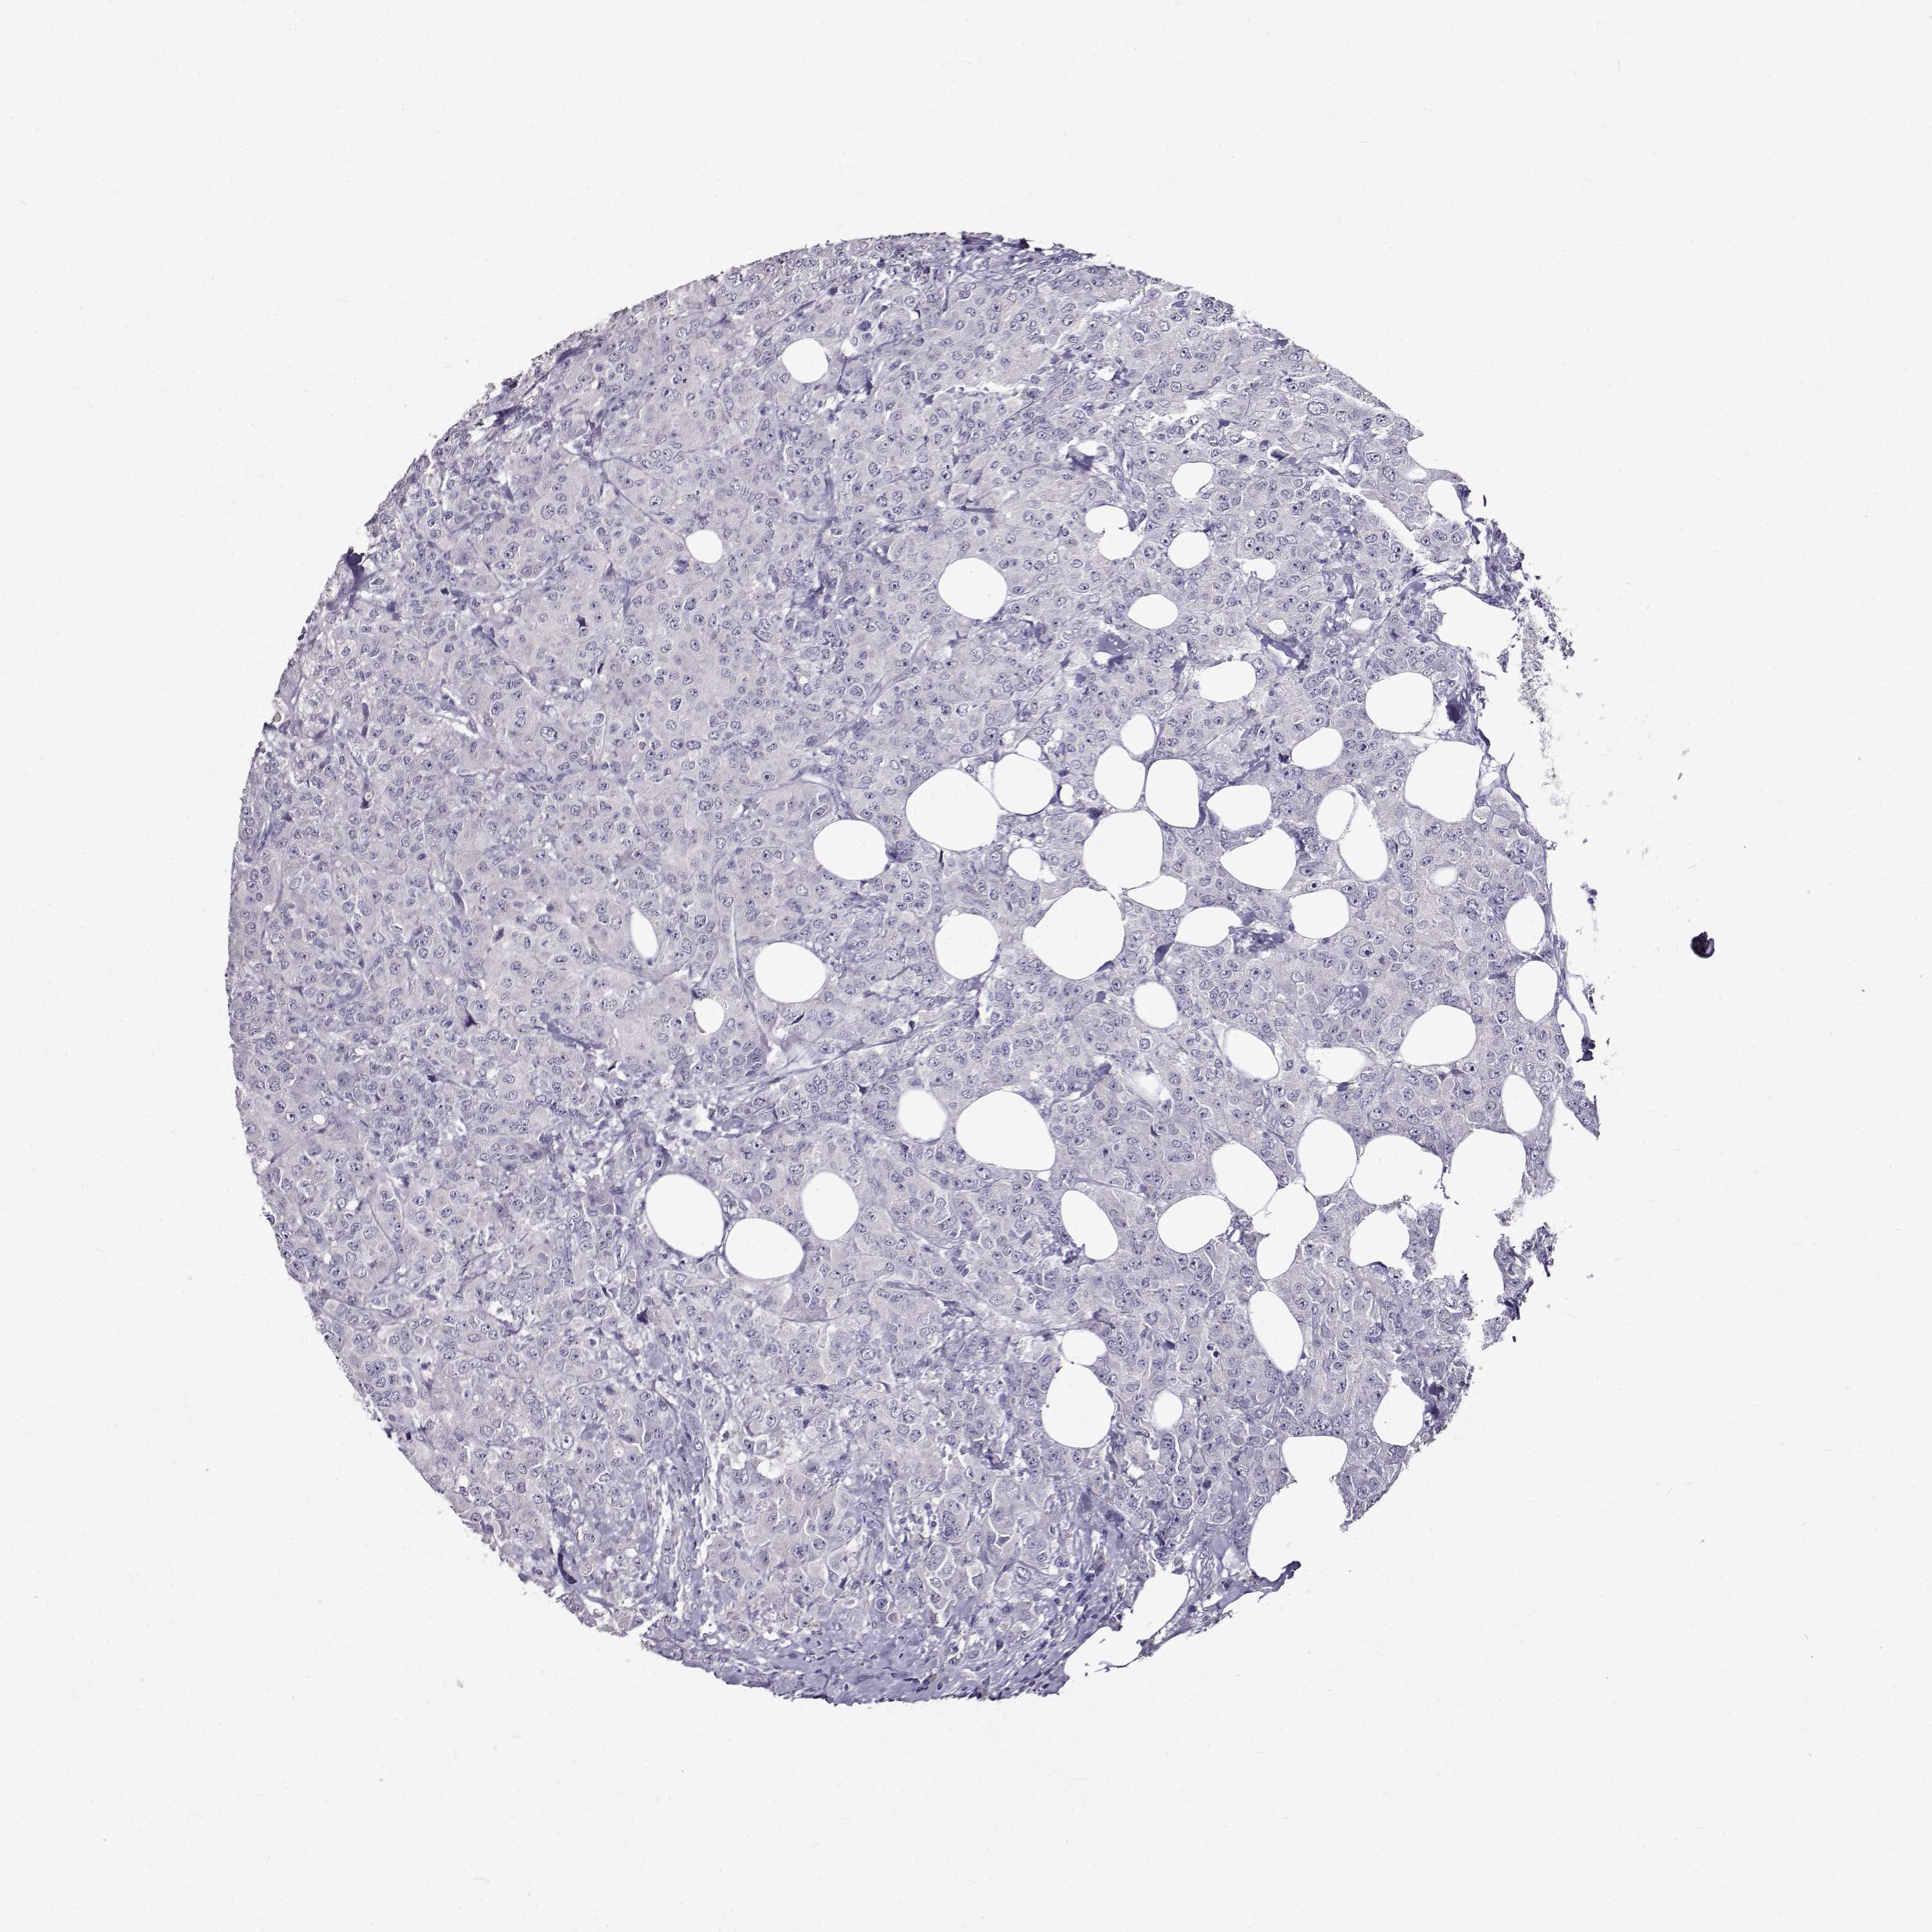

CANCER BREAST CANCER Show tissue menu

BRCA TCGA BRCA VALIDATION PROTEIN EXPRESSION